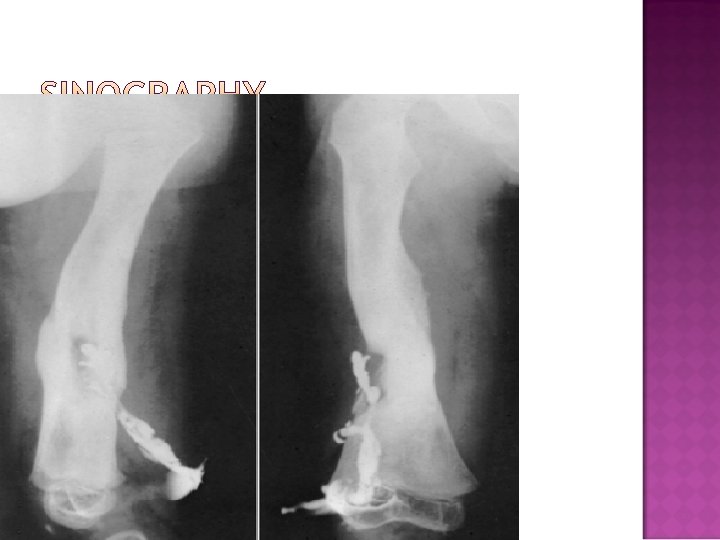

�Plain X rays �Cortical destruction �Periosteal reaction �Sequestra �Sinography